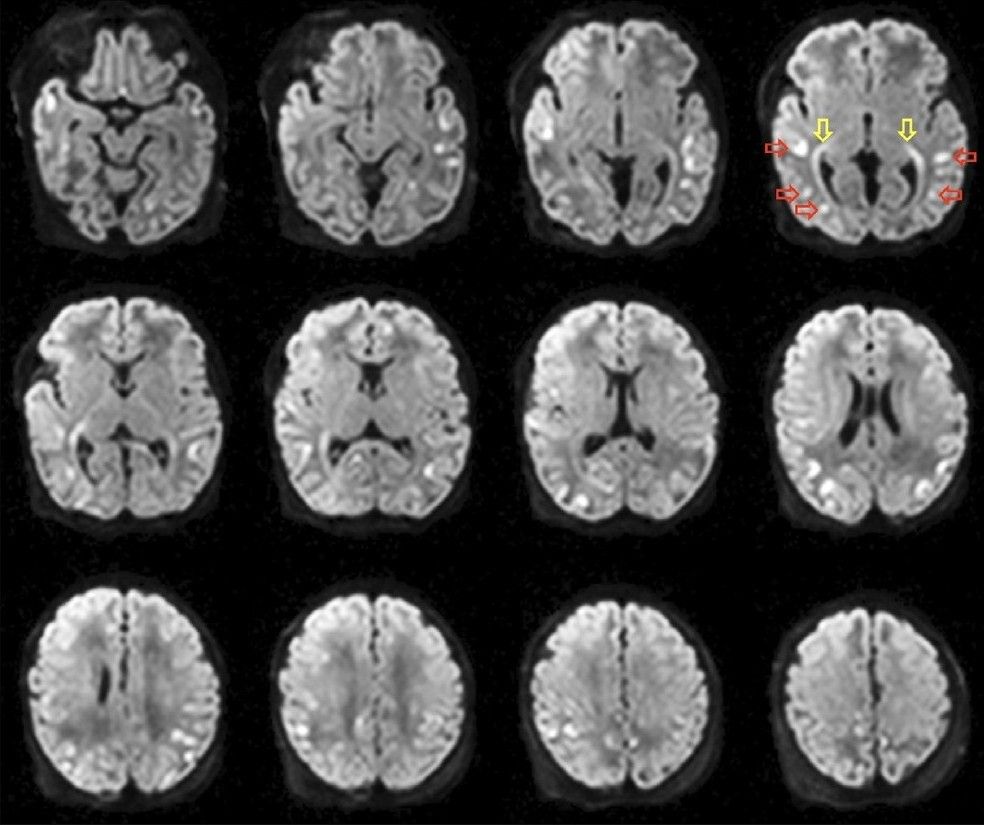

onlinelibrary.wiley.com/doi/10.1111/...

#neuroimaging #neurology #neuroskyence #radiology #diffusion #mri #neuropathy #pain

Free read

onlinelibrary.wiley.com/doi/10.1111/...

#neuroimaging #neurology #neuroskyence #radiology #diffusion #mri #neuropathy #pain

Free read